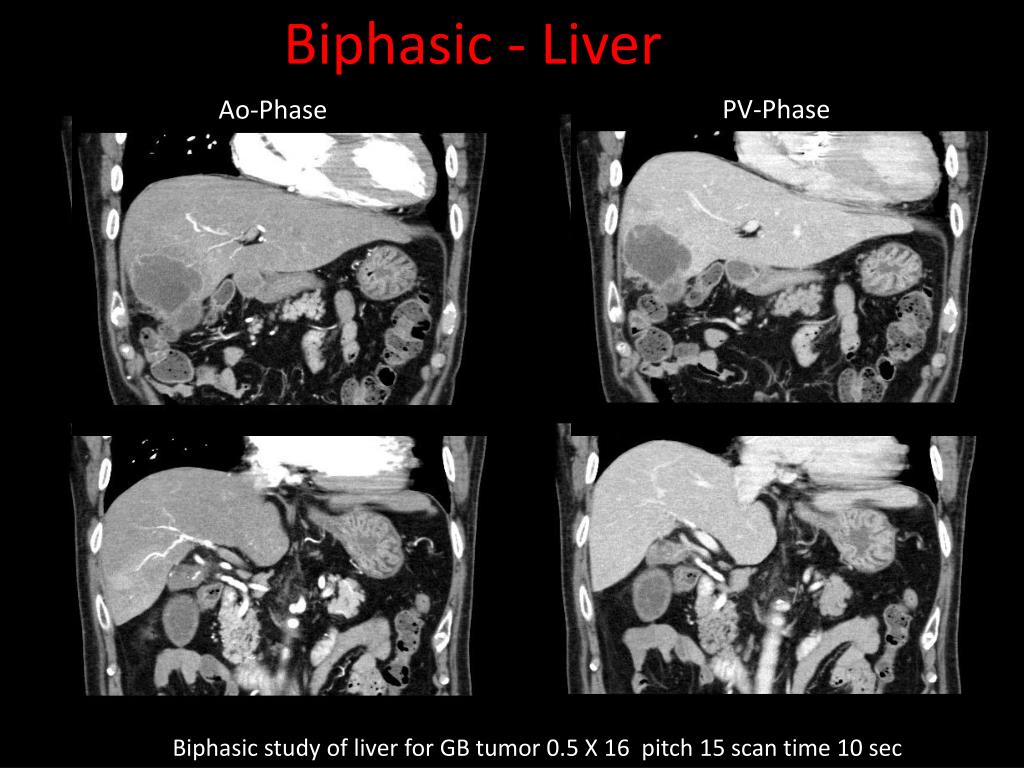

12. Biphasic - Liver PV-Phase Ao-Phase Biphasic study of liver for GB tumor 0.5 X 16 pitch 15 scan time 10 sec